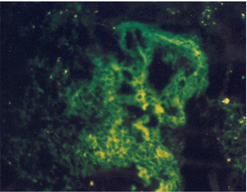

임상증상3

임상증상 설명

사진22 사진23 사진24

설명22 설명23 설명24